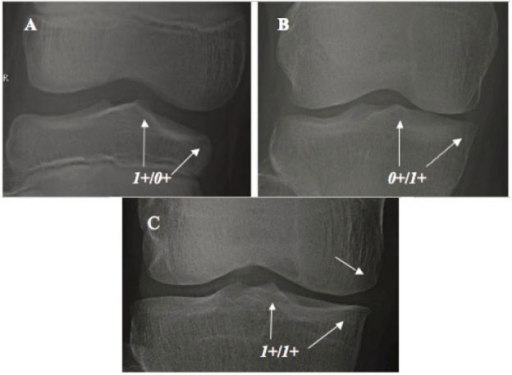

Weight-bearing AP radiograph showing isolated medial compartment osteoarthritis with bone-on-bone changes. Lateral compartment and patellofemoral joint are preserved. Varus deformity appears passively correctable.